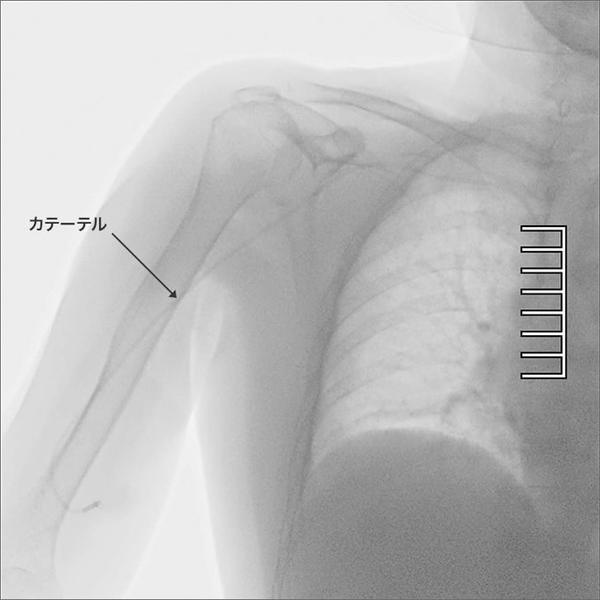

X線を用いた撮影装置で,レントゲンのように静止画を撮影するのではなく,リアルタイムの動画で体の中を透視・撮影する装置。造影剤などを使用することで,血管や臓器が造影される様子を確認しながら撮影することも可能である。主に消化器科や整形外科での検査などで使用されるほか,内視鏡やカテーテルなどの進化により,検査だけではなく治療で使用される機会も増え,幅広い診療科で活用が広がっている。

通常では見ることが難しかった部分のカテーテルも鮮明に観察可能